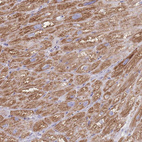

Immunohistochemical staining of human heart muscle shows strong cytoplasm granular positivity in cardiomyocytes.